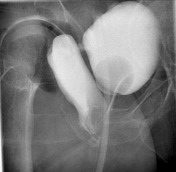

- CT KUB or IV pyelography or Cystoscopy or Retrograde pyelogram

- Retrograde pyelography is the most definitive test to diagnose a ureterovaginal fistula